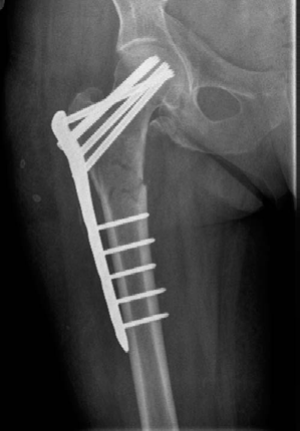

Minute 2 EXAMINER : This woman’s fracture was managed elsewhere and presents during your on-call week with this complication. Can you explain what has happened? (Figures 8.10 and 8.11.) CANDIDATE : This lady was treated with a fixed-angled locking plate. Two things are perhaps responsible for this failure: biomechanics and biology.

Figure 8.11 Anteroposterior (AP) radiograph right femur demonstrating hardware failure, 4 months postoperative.

The implant has been under constant biomechanical load, which has led to the fatigue failure of the implant. In this particular design there is a stress riser at the junction of the last proximal locking hole and the tapered part of the plate, which dictates the failure point in the implant. In addition, the plating device is applied on the lateral aspect of the femur increasing the lever arm for the moment of force as compared with a cephalomedullary device, which further puts the fixed-angle

plating device in this position at a biomechanical disadvantage. Similar results were reported with the use of compression hip screw and 95o plate.2 In this type of fracture an intramedullary device has better results and biomechanical stability.